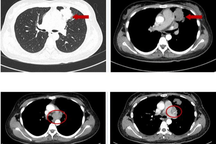

Khối u của bệnh nhân là dạng u máu nằm ở vị trí cạnh vùng nói và vùng trí nhớ của người bệnh (Ảnh bệnh nhân tỉnh sau ca phẫu thuật: BV).

Sau khi hội chẩn, các bác sĩ nhận định đây là ca mổ phức tạp vì khối u dạng u máu nằm ở vị trí cạnh vùng nói và vùng trí nhớ của người bệnh. Việc lựa chọn chiến lược điều trị cũng được tính toán kỹ nhằm đảm bảo lấy bỏ khối u và vùng gây động kinh mà vẫn giữ được các vùng chức năng phát âm, hiểu ngôn ngữ, và vùng trí nhớ.

Rất may mắn khối u của bệnh nhân là lành tính (Ảnh: B.V).